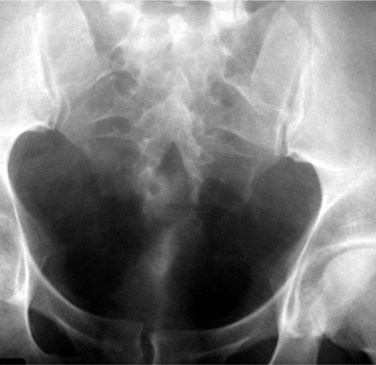

Circumcaval ureter has been classified using different parameters based on intravenous urography or retrograde pyelographic findings. Bateson and Atkinson (1969) classified a ureter with an S-shaped, fish hook, or shepherd’s crook appearance as type I (Fig. 40–19A). The ureter typically overlies or is medial to the lower lumbar vertebral processes and eventually crosses anterior to the iliac vessels, where it then assumes a normal distal course in this setting. A less-angulated “sickle-shaped” ureteral deformity is classified as type II (Fig. 40–19B). The point of maximal obstruction in type I is lateral to the lateral margin of the IVC and is associated with a greater degree of hydronephrosis than type II, in which the point of obstruction is at the lateral border of the IVC (Bateson and Atkinson, 1969). Another classification scheme is based on the level of obstruction; type I crosses at the level of the third lumbar vertebra, and type II crosses at the level of the ureteropelvic junction. The latter may be confused with ureteropelvic junction obstruction (Kenawi and Williams, 1976). The obstruction has been attributed to extrinsic compression of the ureter by the IVC, its lumbar or gonadal branches, or the psoas muscle. However, an intrinsic ureteral abnormality may be contributory as histologic studies of involved ureteral segments have demonstrated fibrotic changes (Kumar and Bhandar, 1985).

Abdominal and flank pain, recurrent urinary tract infection, and hypertension are some of the initial symptoms and signs. A number of cases are now discovered on imaging studies performed to evaluate patients with nonurologic problems (Belis and Milam, 1980; Sener, 1993). The diagnosis should be suspected when the aforementioned pyelographic findings are present (Fig. 40–20A to C). The diagnosis can be confirmed with CT and MRI (Fig. 40–21A and B). Diuretic renography is used to confirm the presence and determine the functional impact of obstruction.

Figure 40–20 A to C. Excretory urography of a patient with type 1 circumcaval ureter.

(Courtesy of Dr. Ronald Zagoria.)